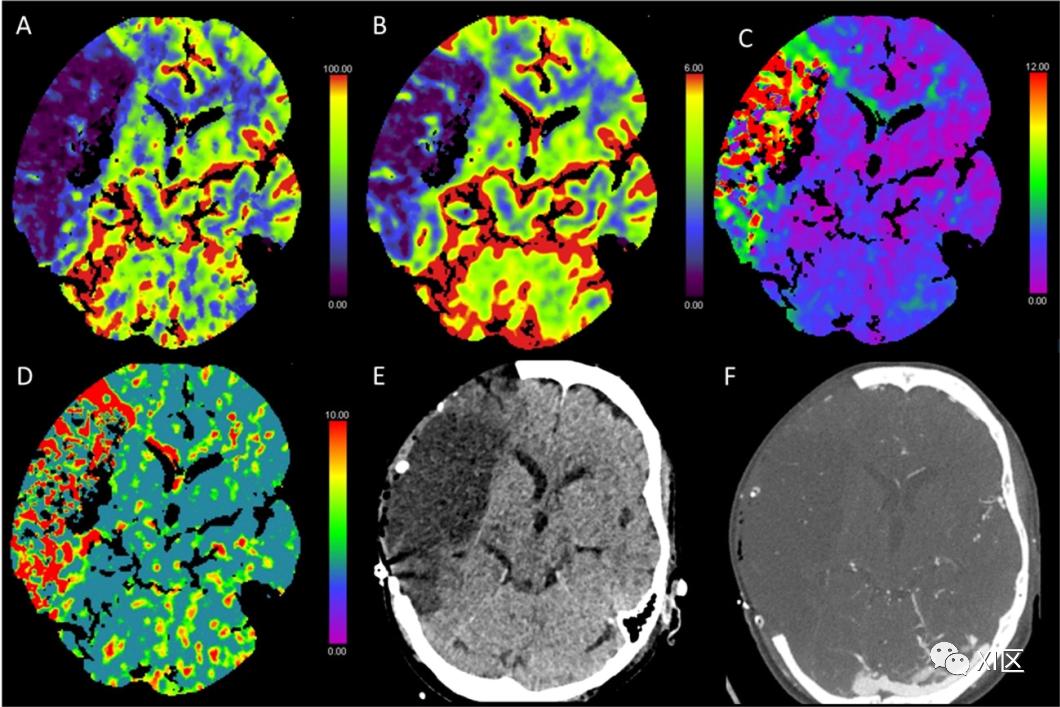

图1、图2、图3和图4给出了急性幕上卒中的例子。图5是一个恶性右侧MCA梗死的随访检查。

图4 脑部CTP产生的彩色编码图:(A)脑血流量(CBF)[mL/100 g/min],(B)脑血容量(CBV)[mL/100 g],(C)Tmax [s],以及(D)平均通过时间(MTT)[s]。(E)NECT和(F)动脉CT血管成像(CTA)。该患者表现为左侧面瘫、失语和右臂瘫痪。NECT显示左侧基底神经节区域开始出现低密度分界,并有轻微肿胀。CBF减少,CBV仅部分减少,Tmax和MTT部分延长,表明是急性梗塞。在CTA检查中,大脑中动脉(MCA)的下动脉主干出现闭塞,这解释了左侧颞叶的Tmax轻微延长。